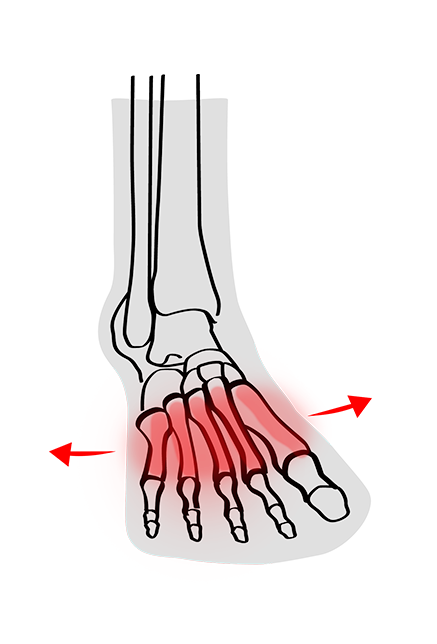

Ein Spreizfuss kann einen oder beide Füsse betreffen und verursacht oft Probleme und Symptome, die den Alltag und die Lebensqualität beeinträchtigen. Unbehandelt kann sich die Fehlstellung des Fusses auf den gesamten Körper auswirken.

Schauen wir uns die Ursachen, Auswirkungen und Behandlungsmöglichkeiten des Spreizfusses einmal genauer an: